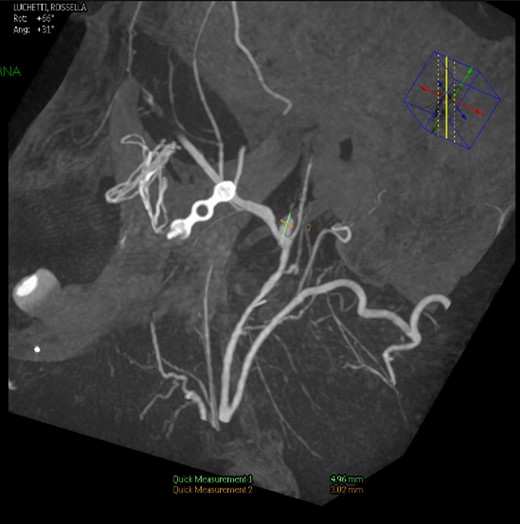

Under general anaesthesia, the right femoral artery was punctured and a guide catheter (5-Fr) was inserted. Selective runs were performed at the left common carotid artery and external carotid artery. The PA was detected at the bifurcation of superficial temporal artery and internal maxillary artery. Through a selective microcatheterization (1.7-Fr), coiling of the lesion and the bifurcation was performed. The final angiograms showed complete exclusion of the PA after coiling, with collateral flow networks that maintained distal patency of the proximally occluded vessels (Fig. 3).